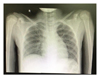

Upon physical examination, the child seemed well but showed signs of mild dehydration such as dry lips and tongue. She was fully alert, and her temperature was 36.7 C, her respiratory rate was 24 breaths per minute, her heart rate was 94 beats per minute, and lung auscultation was unremarkable. There were no inspiratory stridor, suprasternal, epigastric, or intercostal muscle retractions. The laboratory results showed slight leukopenia of 6.290 µl with an unremarkable neutrophil count of 64%, and the absolute lymphocyte was 1700 µl with a neutrophil-lymphocyte ratio of 2.37. A chest X-ray presented an image of a circular foreign object between the cervical-7(C7) to thoracic-1(Th1), possibly in the oesophagus, with no signs of pneumonia (Figure 1). As part of routine screening, a rapid antibody test for SARS-CoV-2 using a serum blood sample (kit: Vivadiag) was carried out, and the results were positive for IgM but negative for IgG. A real-time polymerase chain reaction (RT PCR) nasopharyngeal swab test was positive for SARS-CoV-2 with a cycle time (CT) helicase ORF1ab 33.74 gen RDRP 36.98 (kit: MbiocoV). The entire process from admission to the start of surgery was for 14 hours. The patient was consulted for rigid esophagoscopy and foreign body extraction. The COVID-19 surgical personnel were notified and assembled in the COVID-19 surgical theatre wing.